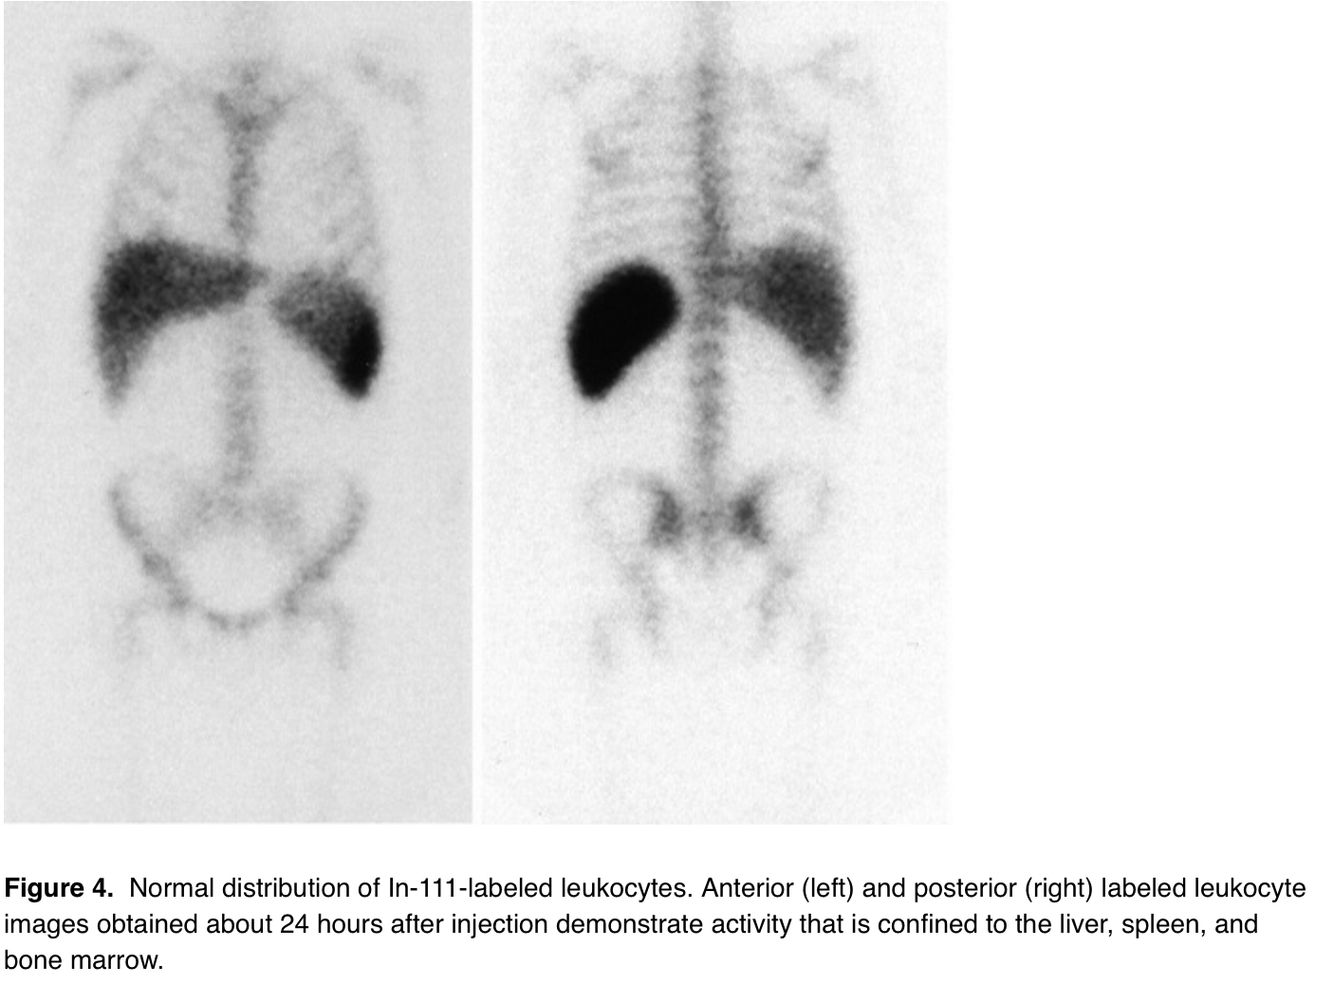

Type of radionuclide: spleen > liver

WBC (very low counts)

• in-111

• technetium 99m

Tag for WBCs

In-111

Image difference between Tc-WBCs and In-WBCs

Indium shows no renal or GI